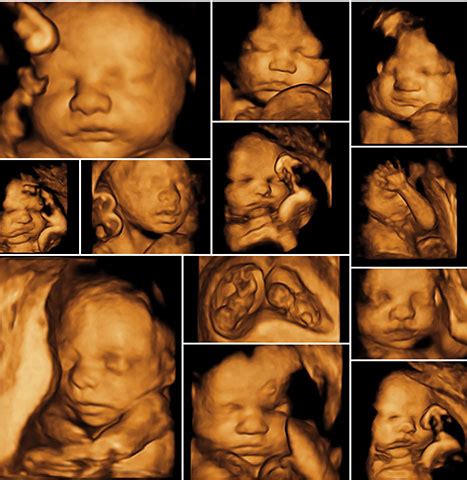

Nad rámec štandardného vyšetrenia sa v Centre fetálnej a gynekologickej diagnostiky JUHAMED s.r.o. v Prešove kladie dôraz na detailné vyšetrenie srdca plodu s využitím najmodernejších 3D/4D ultrazvukových prístrojov. Pri vyšetrení srdca sa používajú pokročilé techniky ako farebné mapovanie, pulzný Doppler, tkanivový Doppler a STIC 4D zobrazenie srdca, ktoré umožňujú komplexné posúdenie morfológie a funkcie srdca.

Na rozdiel od bežných 2D morfologických vyšetrení, centrum realizuje u každého plodu aj 3D vyšetrenie mozgu pomocou tomografického ultrazvukového zobrazenia. Toto vyšetrenie umožňuje zobrazenie mozgu plodu v 0,5 mm rezoch v troch na seba kolmých rovinách, podobne ako pri magnetickej rezonancii alebo CT, avšak s využitím ultrazvuku.